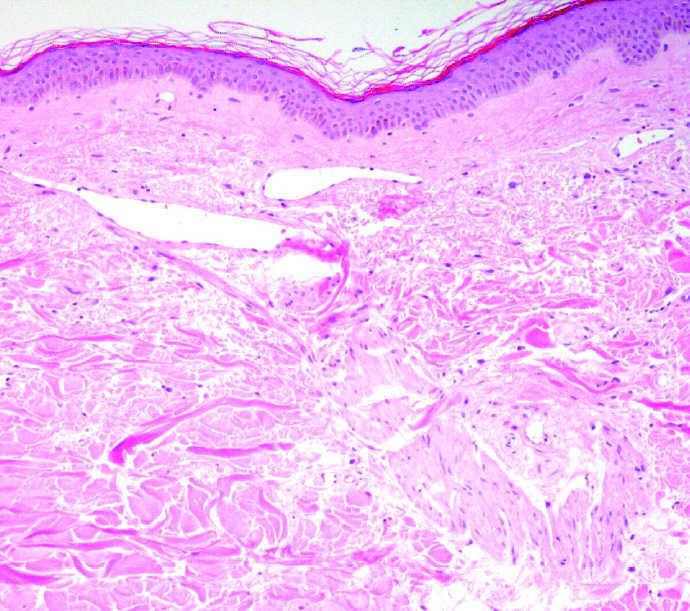

La paciente fue tratada con láser de colorante pulsado V-Beam, Candela corp. (595 nm). Recibió 5 sesiones (una sesión mensual) de láser (pulso de 3 ms, diámetro de impacto de 7 mm y energía 7 J/cm 2 en las primeras 2 sesiones y 12 J/cm 2 en las tres siguientes). Los parámetros de enfriamiento fueron 30-30 (criógeno de 30 ms de duración con un retardo de 30 ms). No se precisó anestesia. Tras cada sesión la paciente desarrollaba púrpura inmediata que se resolvía en 10 a 12 días. Una biopsia de un lesión purpúrica mostró dilatación y congestión del plexo vascular (fig. 3).

Fig. 3.--Una biopsia de un lesión purpúrica mostró dilatación y congestión vascular. (Hematoxilina-eosina, ×20.)

Nuestra paciente recibió tratamiento con el LCP, Candela corp. de 595 nm utilizando pulsos ultralargos de 3 ms. Tuvimos la oportunidad de realizar estudios histológicos que se correlacionaban con la clínica y con el modo de acción del LCP. Las telangiectasias son vasos dilatados, tal y como encontramos en la biopsia pretratamiento. La presencia de fibroblastos de morfología estrellada es típica de la piel radiada. Inmediatamente después del tratamiento con LCP aparece la púrpura. En una biopsia realizada en ese momento encontramos congestión vascular sin daño epidérmico. Los pulsos de alta energía, como los utilizados con el LCP, producen coagulación intravascular sin daño perivascular 2. La epidermis está respetada y los vasos superficiales de la dermis papilar y reticular contienen eritrocitos aglutinados, fibrina y trombos plaquetarios 2, tal y como se vio en nuestro caso. En la biopsia que se tomó un mes después del tratamiento no se observaron vasos anómalos ni cicatrices, ya que los vasos tratados con el LCP son destruidos y reemplazados lentamente por vasos normales 2. Clínicamente logramos un resultado muy satisfactorio en 5 sesiones sin efectos secundarios. El tratamiento fue bien tolerado y la paciente quedó contenta con el resultado.